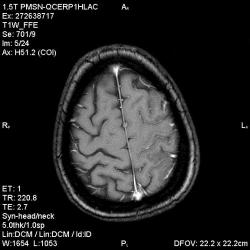

Из анамнеза - Женщина 45 лет. За год похудела на 15 кг (со слов матери), в последние месяцы случались эпизоды потери сознания. Онкозаболеваний и прочая в анамнезе нет. Сознание спутанное, из особенностей в анализах только подъем амилазы крови.

"Раскрою" карты. Мы подумали о синдроме MELAS (mitochondrial encephalomyopathy, lactic acidosis and stroke) - дословно, митохондриальная энцефаломиелопатия, лактоацидоз и инсульт. В качестве дифференциальной диагностики можно было бы предположить вирусный энцефалит, но опять-таки, расположение очагов смущает - только с одной стороны и в абсолютно различных структурах.

В данном случае мы видим импульную последовательность FLAIR - режим с подавлением сигнала от воды, поэтому ликвор гипоинтенсивен, а также (вторая серия) - изображения, взвешенные по T1 после введения контрастного препарата. На T1 жидкость (ликвор) также представляется гипоинтенсивной. Зато на этих сериях гиперинтенсивны сосуды, т.к. контрастное вещество циркулирует в кровяном русле.

Что касается "белых" костей свода черепа, так это не кости, а кожа и подкожная клетчатка. Кости - глубже, "серовато-черные".

Изменения носят сосудистый характер. Процесс достаточно острый, имеется объемное воздействие, борозды левой гемисферы компремированы. По поводу MELAS синдрома очень сомневаюсь, почему поражена только левая гемисфера? Надо делать МР-ангиографию, смотреть нет ли стеноза

MELAS синдром - дебютирует с детских лет, характерен целый комплекс неврологических проявлений, заболевание генетическое, поражение системное, хотя есть множество вариантов митохондриального поражения, все же сомнительно. Хотелось бы акцентировать внимание, что гиперинтенсивные очаги есть в мозолистом теле, поражены выражено перивентрикулярные отделы, U -пути, белое вещество, поэтому так категорично демиелинизацию не вычеркивала бы из дифряда ( хотя тоже нетипично односторонее поражение). Думаю, для объективных выводов все же мало общей информации о пациентке, были ли клинические эпизоды раньше, чем объяснить такую потерю веса (возможно есть проявление паранеопластического синдрома?). Ну и МРТ-контроль в динамике, ангиография.

Да, неоднозначный случай. Точно не РС и не ОНМК. Я бы написала асимметричную лейкоэнцефалопатию неясного генеза. Можно было бы думать о лимфоме (полифокальное поражение, да еще мозолистое тело вроде бы задействовано (эх, сагиттальчики бы)). Но! Учитывая отсутствие накопления КВ.... Ну и надо исключать интоксикацию, всяческие аутоиммунные процессы (в т.ч. и васкулиты), сахарный диабет, ну и естественно наследственную патологию обменных процессов. УУУх! Вот.......

Имхо ишемический онмк в бассейне сма. Особенно показательны 5-й и 6-й файлы, отграничение как раз на границе бассейнов средней и перикаллёзной. Плюс одностороннее поражение.